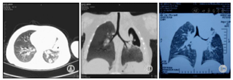

4例X线检查均示肺实质病变。例1,病程11 d CT示右上肺片状高密度影,病程20 d CT示双肺多个大小不等囊状影,右上肺显著。见图1A、图1B;3个月后复查胸片肺炎基本吸收,见图1C。例2,病程15 d肺CT:左侧胸廓略塌陷,左肺上叶大片状密实影,内见液平囊状影,见图2A、图2B;18个月后复查肺CT示左上肺脓肿消失,留有部分肺不张、条索影,见图2C。例3,病程6 d胸片示右上肺大片状高密度影,病程17 d肺CT示右上中肺大片及点状高密度影,右下肺背段多个厚壁空洞,呈簇状沿支气管分布,纵隔淋巴结大,见图3A、图3B。3个月后复查胸片肺炎基本吸收,见图3C。例4,病程5 d胸片示左上肺组织坏死,见图4A。0.5年后复查胸片提示炎症较前明显吸收,见图4B。

注:A:2010-01-16胸片示右上肺片状高密度影;B:2010-01-26 CT示右肺呈蜂窝状;C:2010-03-30胸片示右上肺炎基本吸收